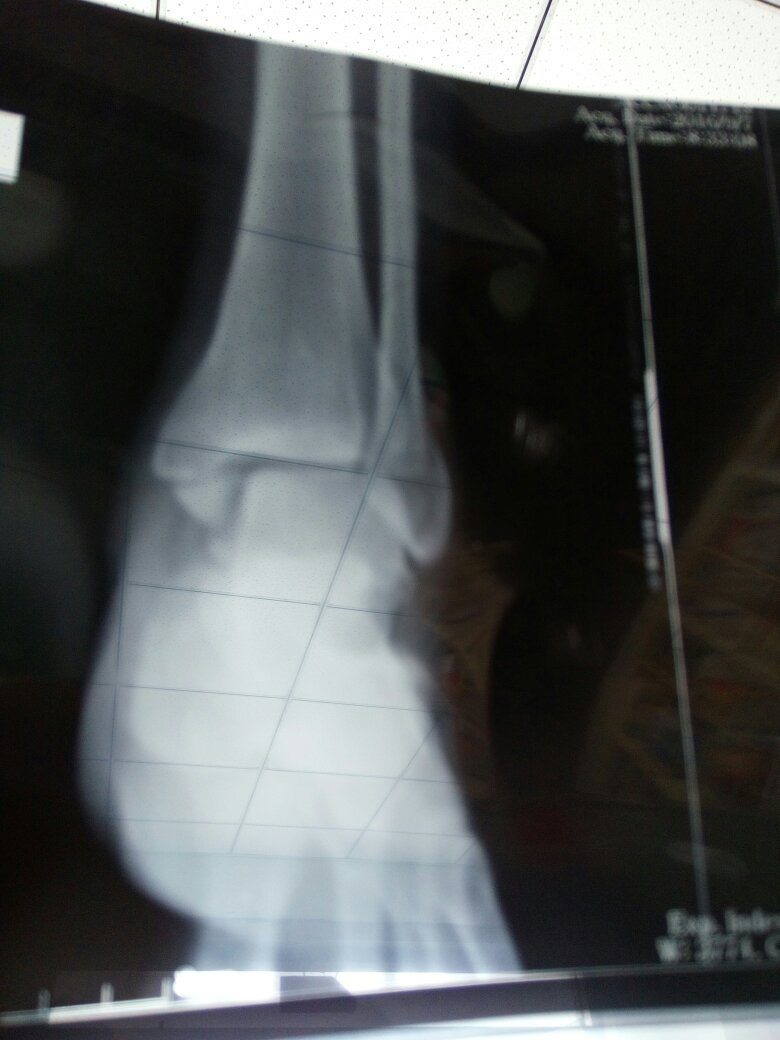

怀孕七个月了,左脚踝两边骨折,到生孩子时候能慢慢走路吗?后面有片子帮我看看吧 谢谢 点击展开 133*****340_heC3 2016-09-23 10:10 满意回答 您好,根据描述,考虑可以寸细评石膏外固定。怀孕期间,尽量不做。拍径劣片概豆放射检查 cn#afBBaVapka 2016-09-23 10:14 宝宝知道提示您:回答为网友贡献,仅供参考。 相关问题 那要是脚踝怀疑骨折,是拍什么片子呢 你好,我在排卵期陪我儿子拍脚踝骨折片子,现在怀孕42天了 脚趾骨折57天了,脚踝还是肿,现在可以下地走路了吗?同房影响恢复吗?拿热水泡脚有好处吗?谢谢